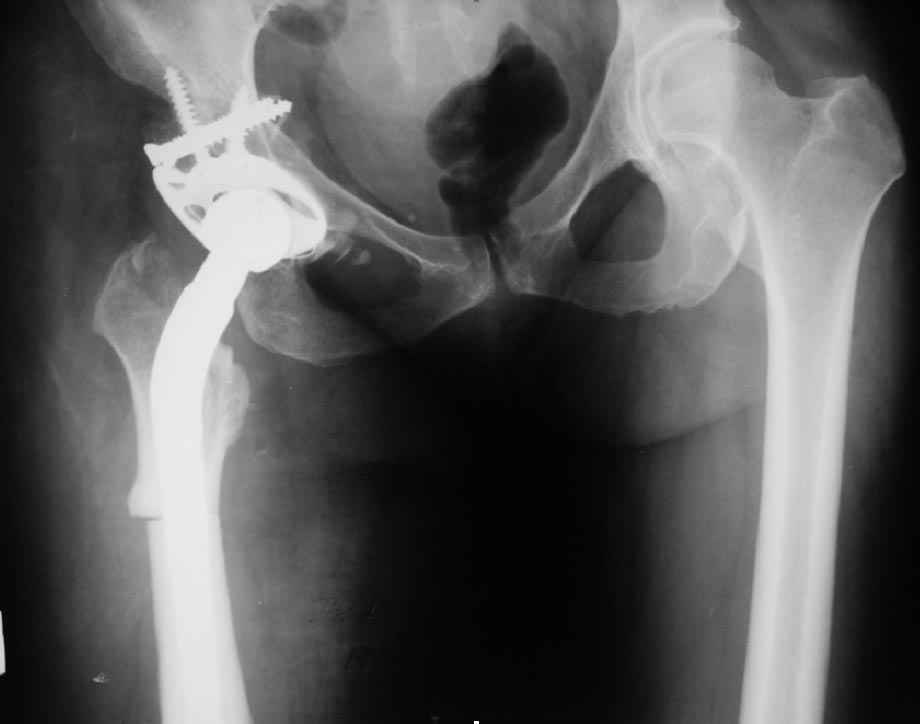

В прищепке случай 1999 года - эндопротезирование после операции Шанца

Илизарова. Возраст пациентки 45 Коррекция была в 17 лет.  А Рыков Хабаровск.

Пациентка 51 года обратилась с жалобами на выраженные боли в правом т/б

суставе. Болеет с детства. В возрасте 10 лет коррегирующая вальгизирующая

остеотомия вертельной области правой бедренной кости. В 2001 году тотальное

гибридное протезирование левого т/б сустава.

из возможных вариантов решения возможно коррегирующая варизирующая

остеотомия правой бедренной кости с дальнейшим тотальным протезированием

(механика?) с удлиненным бедренным компонентом.